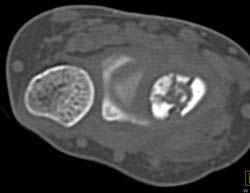

Trauma With Axillary Artery Not Injured